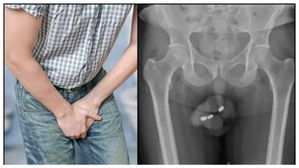

అతడు లైంగిక ఆనందం కోసం పురుషాంగంలో బ్యాటరీ తగిలించుకున్నాడు.. చివరికి ఏం జరిగిందో చూడండి!